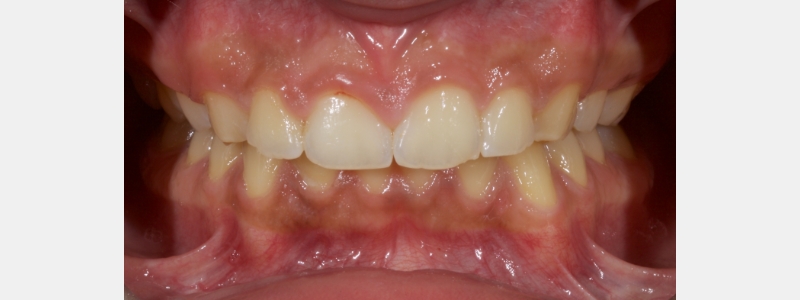

A diagnosis of altered passive eruption (APE) alongside tooth surface loss (TSL) secondary to parafunction was made for a referred female patient in her early 20s who complained of having“short, fat, baby teeth.” Due to her age, she was treated with a simple gingivectomy (after bone sounding), nightguard vital bleaching (NGVB), and additive edge bonding.

The worn incisal edges were restored with edge bonding, a new technique for restoring worn dentition. This should be regarded as a multiple Class IV restoration.